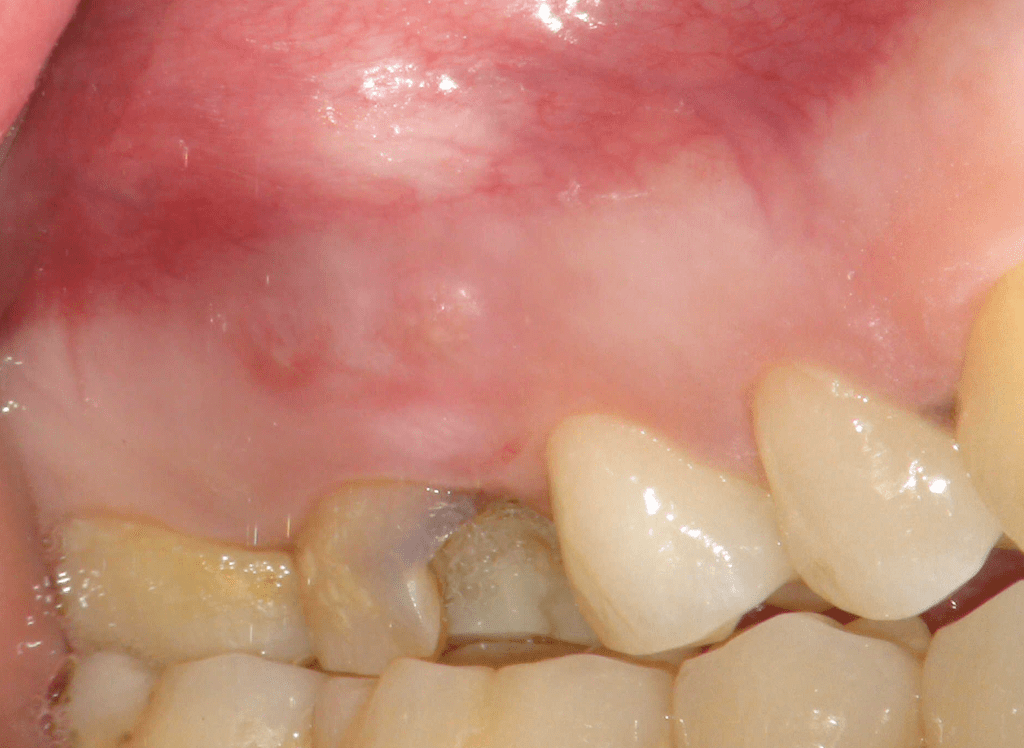

Reco pared vesticular